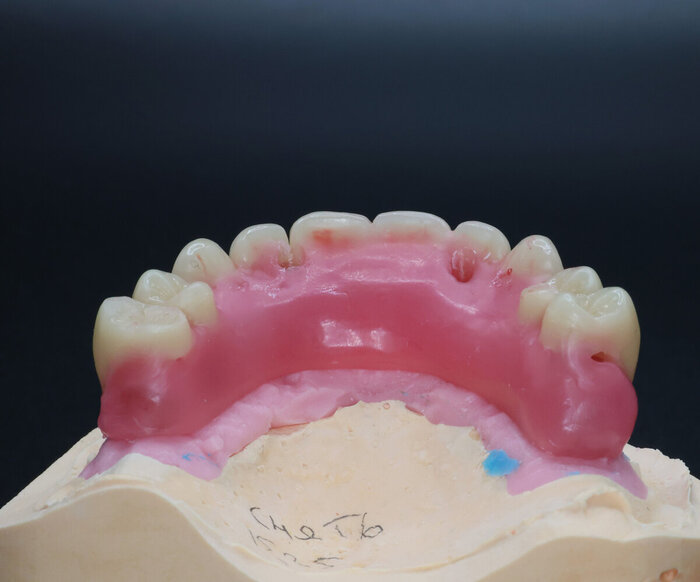

Розовый пластик - он не только спереди, он ещё и за зубами.

Временный протез "всё на 4-х", постановка на воске

На фото выше - воск. Протез временный будет поизящнее. Постоянный, когда до него дойдёт, ещё более гладкий и аккуратный получится.